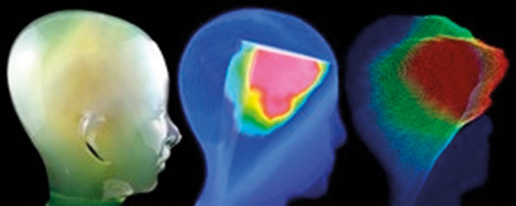

Wprowadzenie Rozwój nowych technik leczenia w teleradioterapii, opartych na modulacji intensywności dawki promieniowania, radiochirurgii i stereotaksji wymaga coraz wyższej jakości realizowanego leczenia. Zapewnienie odtwarzalności planu leczenia bazującego na obrazie statycznym i jego realizacja w warunkach rzeczywistych wiążą się z koniecznością zapewnienia nowych narzędzi, które pomogą dokładniej zweryfikować i zrealizować geometrię planu terapeutycznego. Równolegle z rozwojem technik radioterapeutycznych równie dynamicznie…